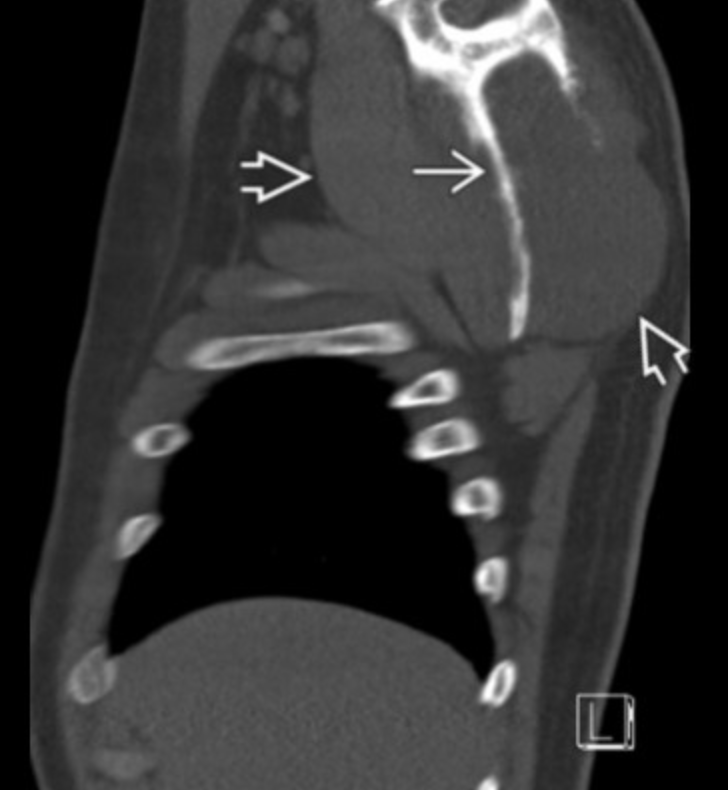

PAR-osteal Osteosarcoma

• Age 20-50 yo

• Looks like densely calcified mess of shit

• Metaphysis

• Posterior distal femur

• String sign

• Lucent line separates calcific mass from the cortex of bone

• Lower grade

• Best prognosis of the osteosarcomas

• Reverse Zonal Ossification

• Central area of calcification that over time will have increased and progressively calcification grow around it

• Opposite of zonal ossification seen in myositis ossificans which has a peripheral ring of calcification which then fills in with calcifications moving inward